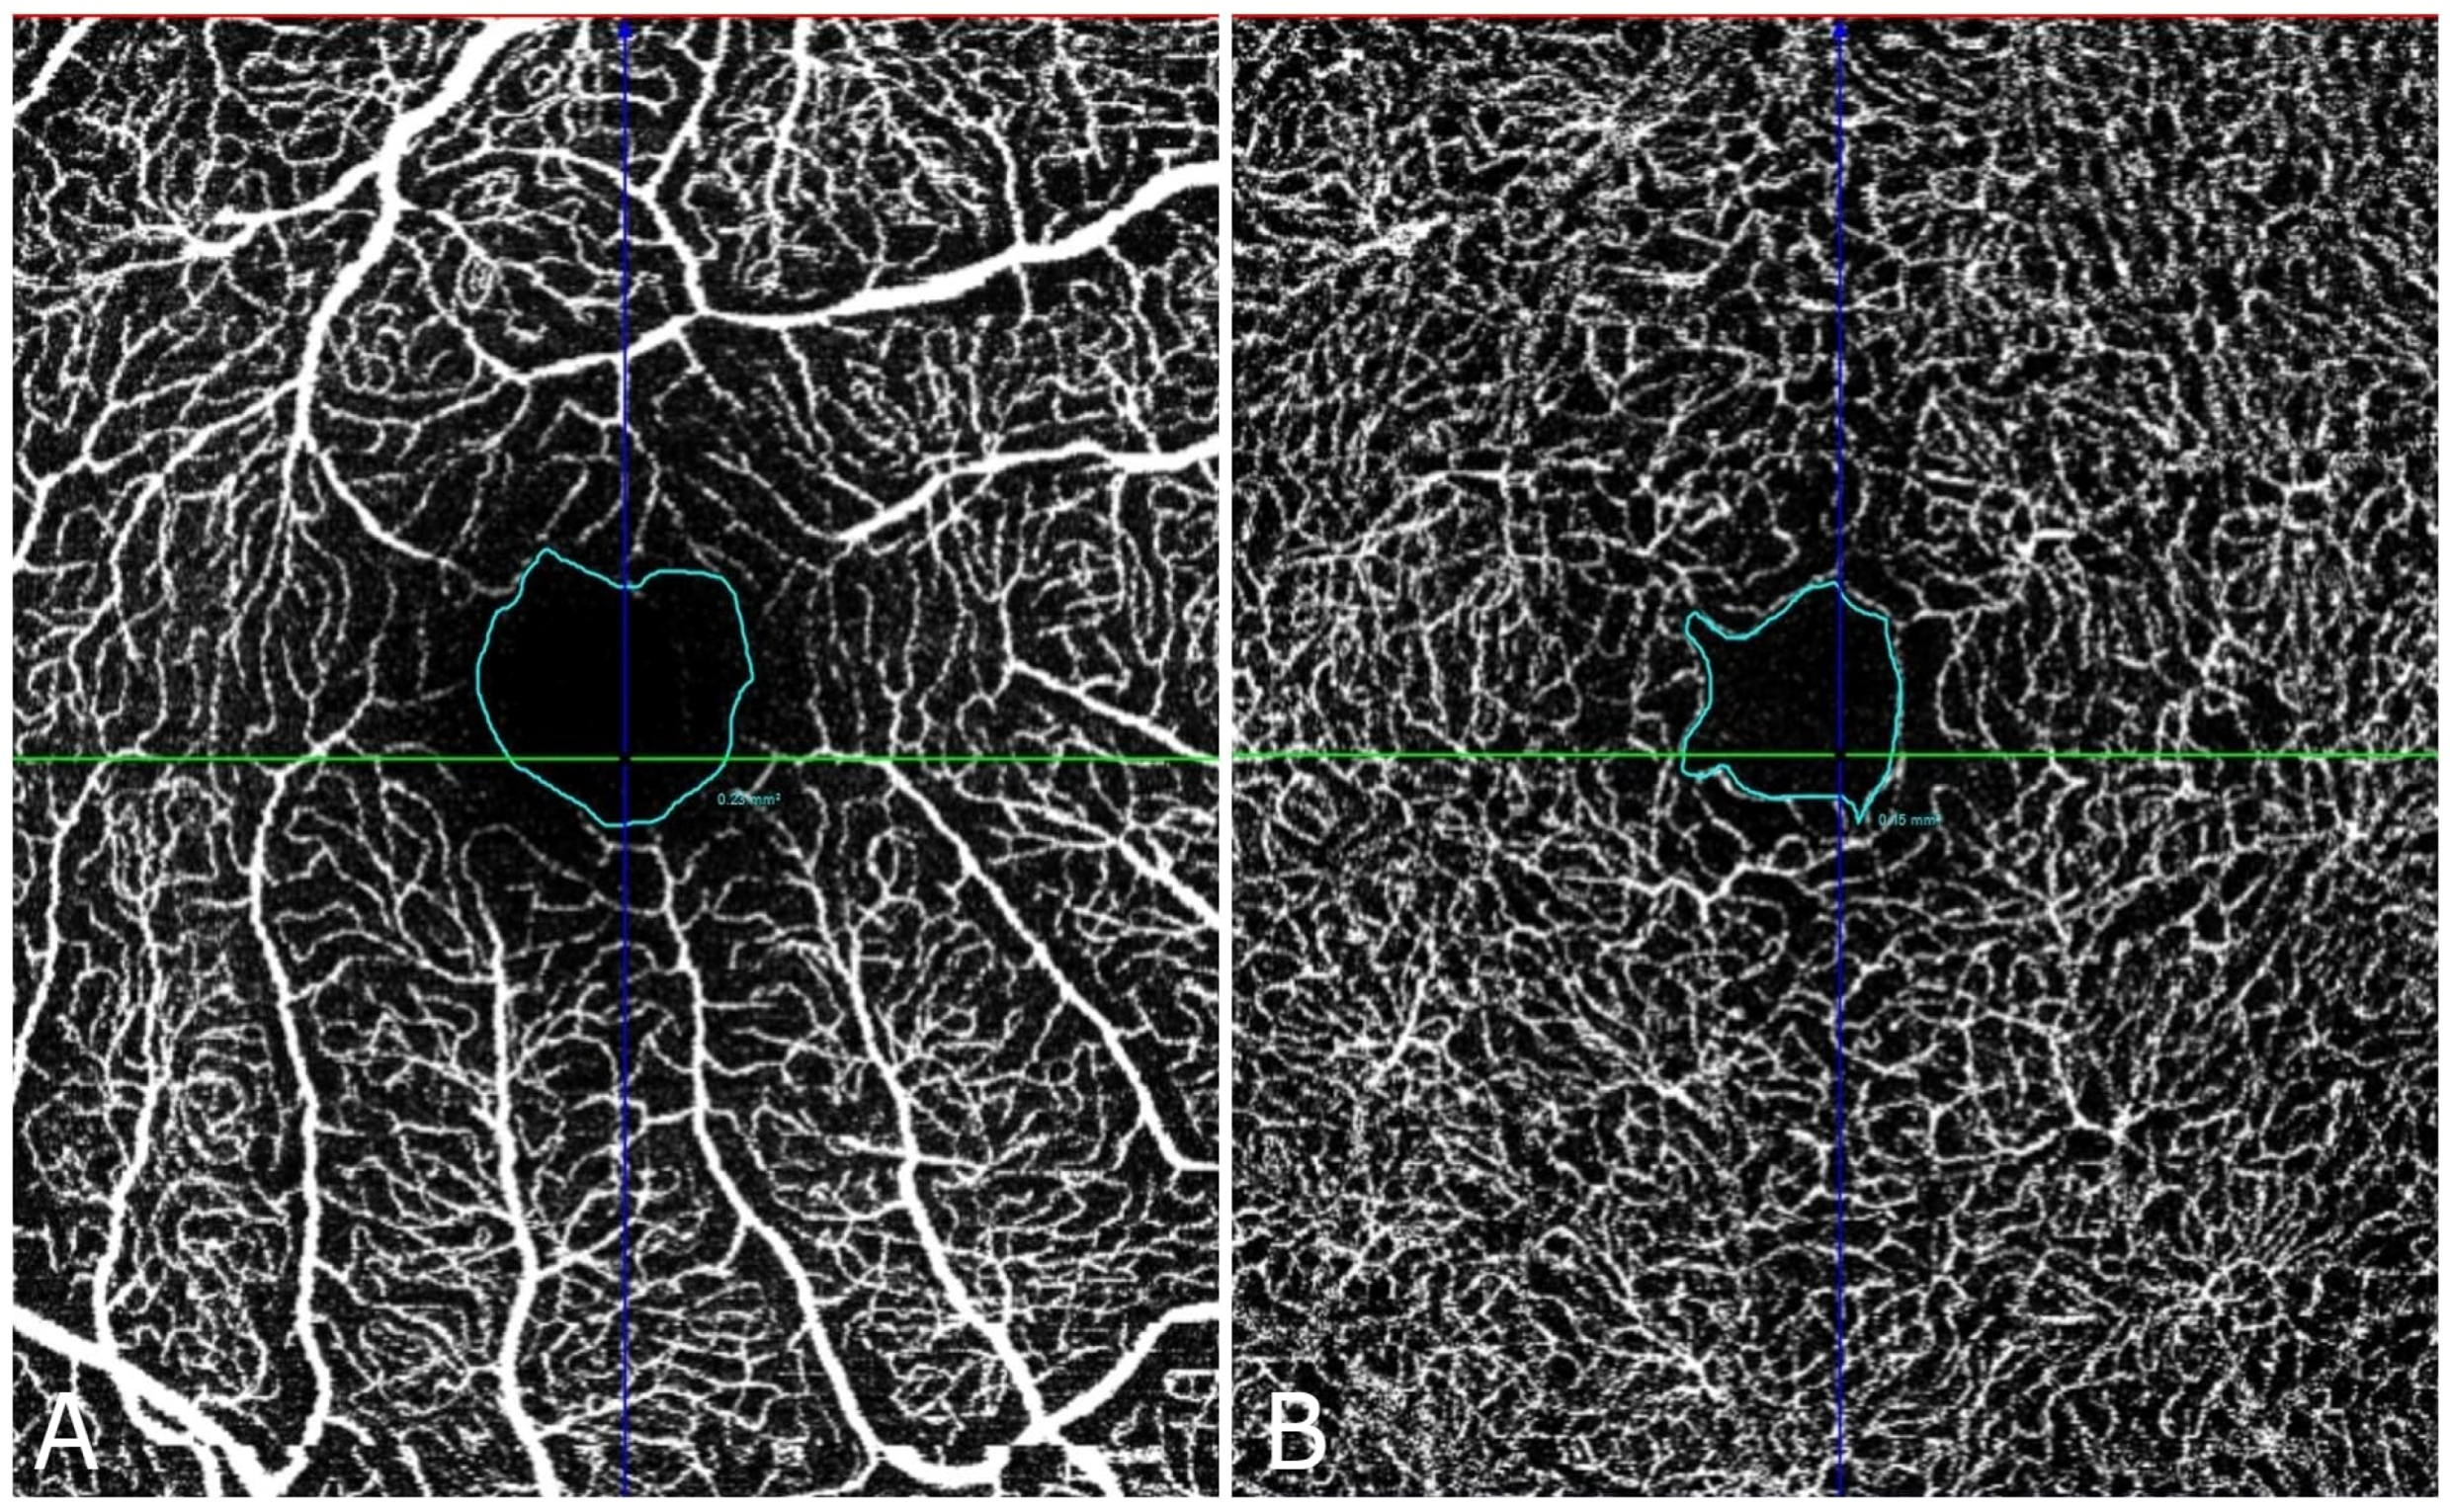

Both superficial and deep FAZ areas were significantly larger in diabetic patients compared to controls (p < 0.05), indicating vascular alterations associated with diabetes. The mean superficial FAZ value for the diabetes group was 0.37 mm2 (SD = 0.17 mm2, range = 0.20–0.53 mm2) and 0.26 mm2 (SD = 0.08 mm2, range = 0.19–0.35 mm2) for the deep FAZ. For the control group, the superficial FAZ was 0.21 mm2 (SD = 0.07 mm2, range = 0.20–0.32 mm2) and deep FAZ was 0.18 mm2 (SD = 0.06 mm2, range = 0.14–0.16 mm2). The 95% confidence interval (CI) for the superficial FAZ value in the DM group was 0.21–0.53 mm2 and 0.12–0.32 mm2 for the control group. For deep FAZ, the 95% CI in the DM group was 0.20–0.31 mm2, while for the control group, it was 0.12–0.28 mm2. Figure 2 and Figure 3 shows the FAZ in the control group (A) is smaller and well-defined, while in the diabetic group (B), the FAZ is larger and irregular, reflecting the vascular changes associated with diabetic retinopathy. Table 1 presents the FAZ area measurements (in mm2) for both superficial and deep capillaries in both groups.

Figure 3. OCT angiography: FAZ area in the deep (A) and superficial (B) vascular plexus in the diabetic patient is larger and irregular, with a notable expansion in both superficial and deep zones. Scale bar = 200 µm.